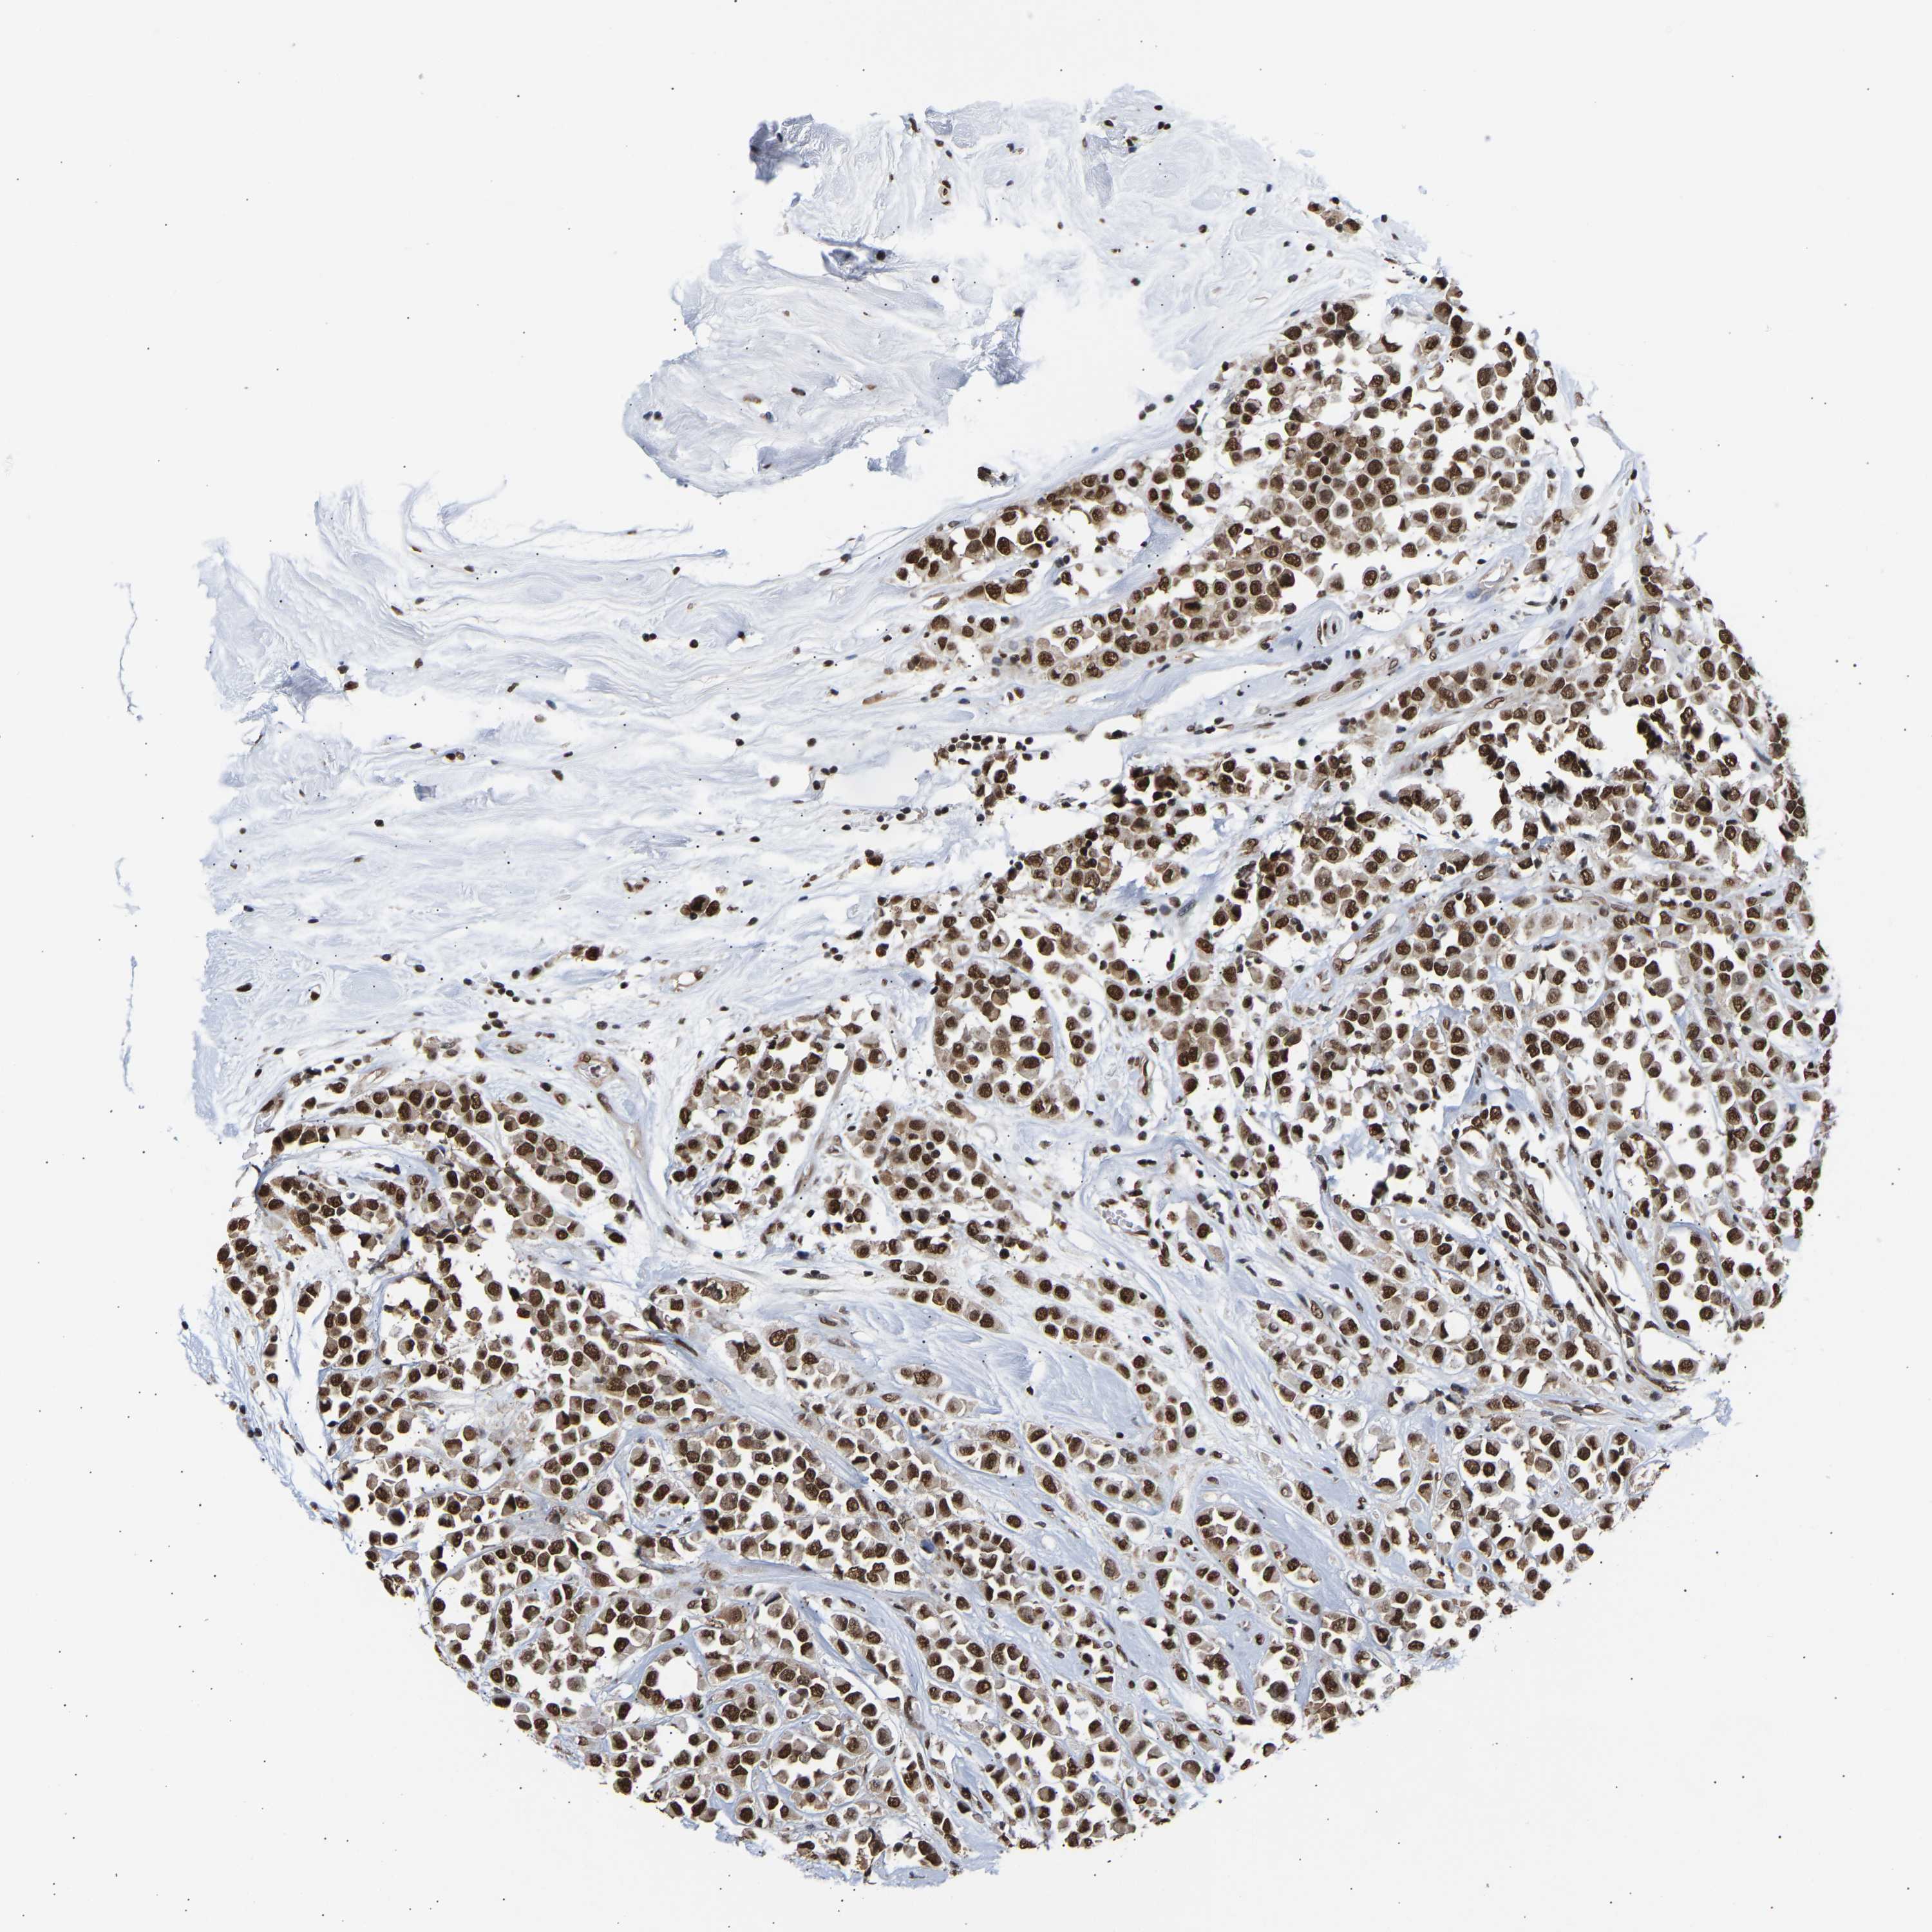

CANCER BREAST CANCER Show tissue menu

BRCA TCGA BRCA VALIDATION PROTEIN EXPRESSION